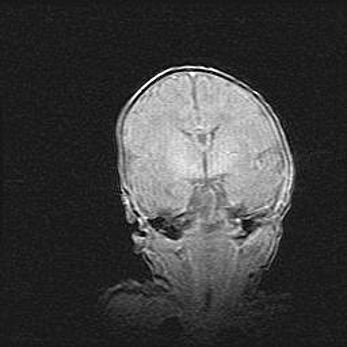

Подострая гематома правой гемисферы мозжечка.

Наружная гидроцефалия.

Возраст: 15 дней

Вес: 3100 г

Пол: женский

Окружность головы: 37 см

Срок гестации: 35-36 недель

При открытой наружной форме гидроцефалии у новорожденных расширяются и переполняются субарахноидные пространства.

Кровоизлияния в мозжечок имеют две клинико-анатомические формы: полушарные гематомы и кровоизлияния в червь.

К появлению этой патологии может привести: повреждения головного мозга, возникающие в результате асфиксии и гипоксии плода при беременности, или травмы во время родов. Редко гематома мозжечка может быть результатом первичной коагулопатии и сосудистой мальформации, диссеминированном внутрисосудистом свертывании, изоиммунной тромбоцитопении.